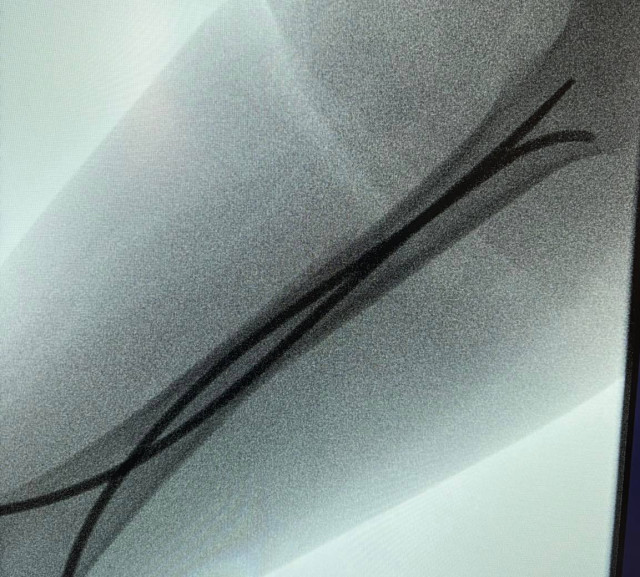

Інтрамедулярний остеосинтез – хірургічний метод лікування переломів, що дає можливість уникнути тривалого носіння гіпсових пов’язок та швидко реабілітуватися. Цей метод полягає у введенні в кістку гнучких титанових стержнів, які виконують функцію внутрішнього каркаса та фіксують кісткові відламки. Оперативне втручання проводять під рентген-контролем.